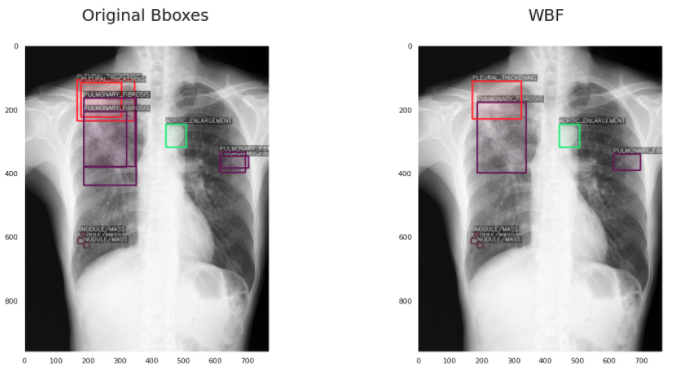

5、加权框融合(WBF)后处理,0.226 mAP (+15%)

这对我来说也是一个全新的想法,在网上很难找到。加权框融合是一种对目标检测模型产生的框进行过滤,从而使结果更加准确和正确的技术。它的性能超过了现有的类似方法,如NMS和soft-NMS。具体内容我会在另一篇文章介绍。应用WBF的结果是这样的: